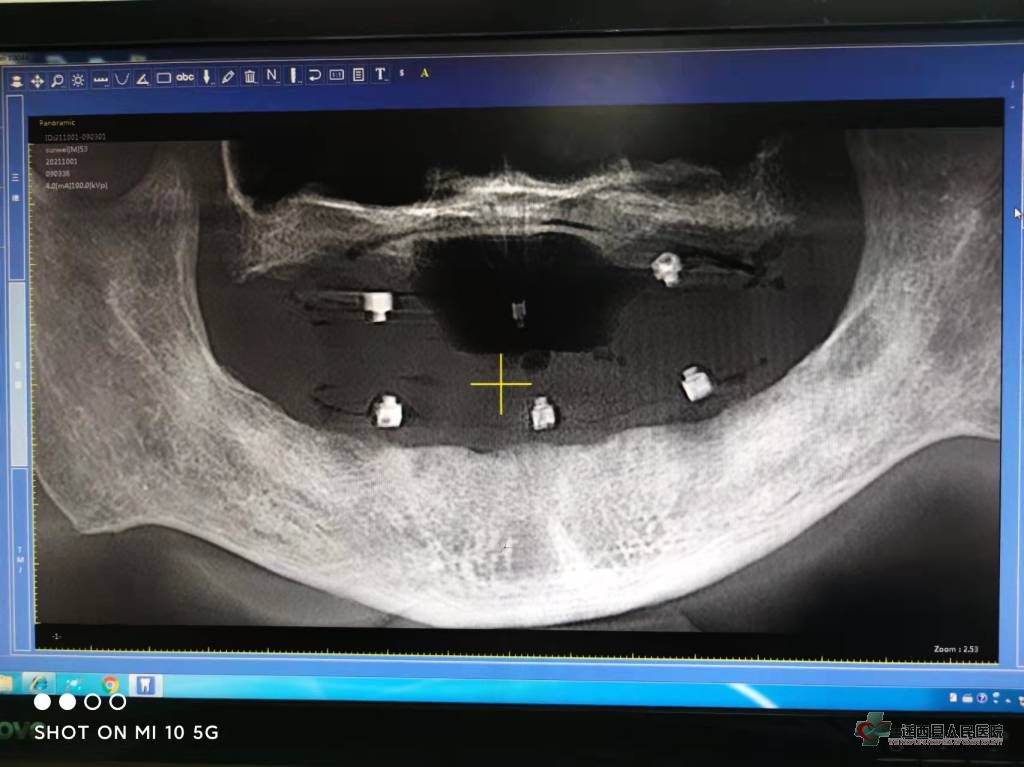

戴入种植导板CBCT